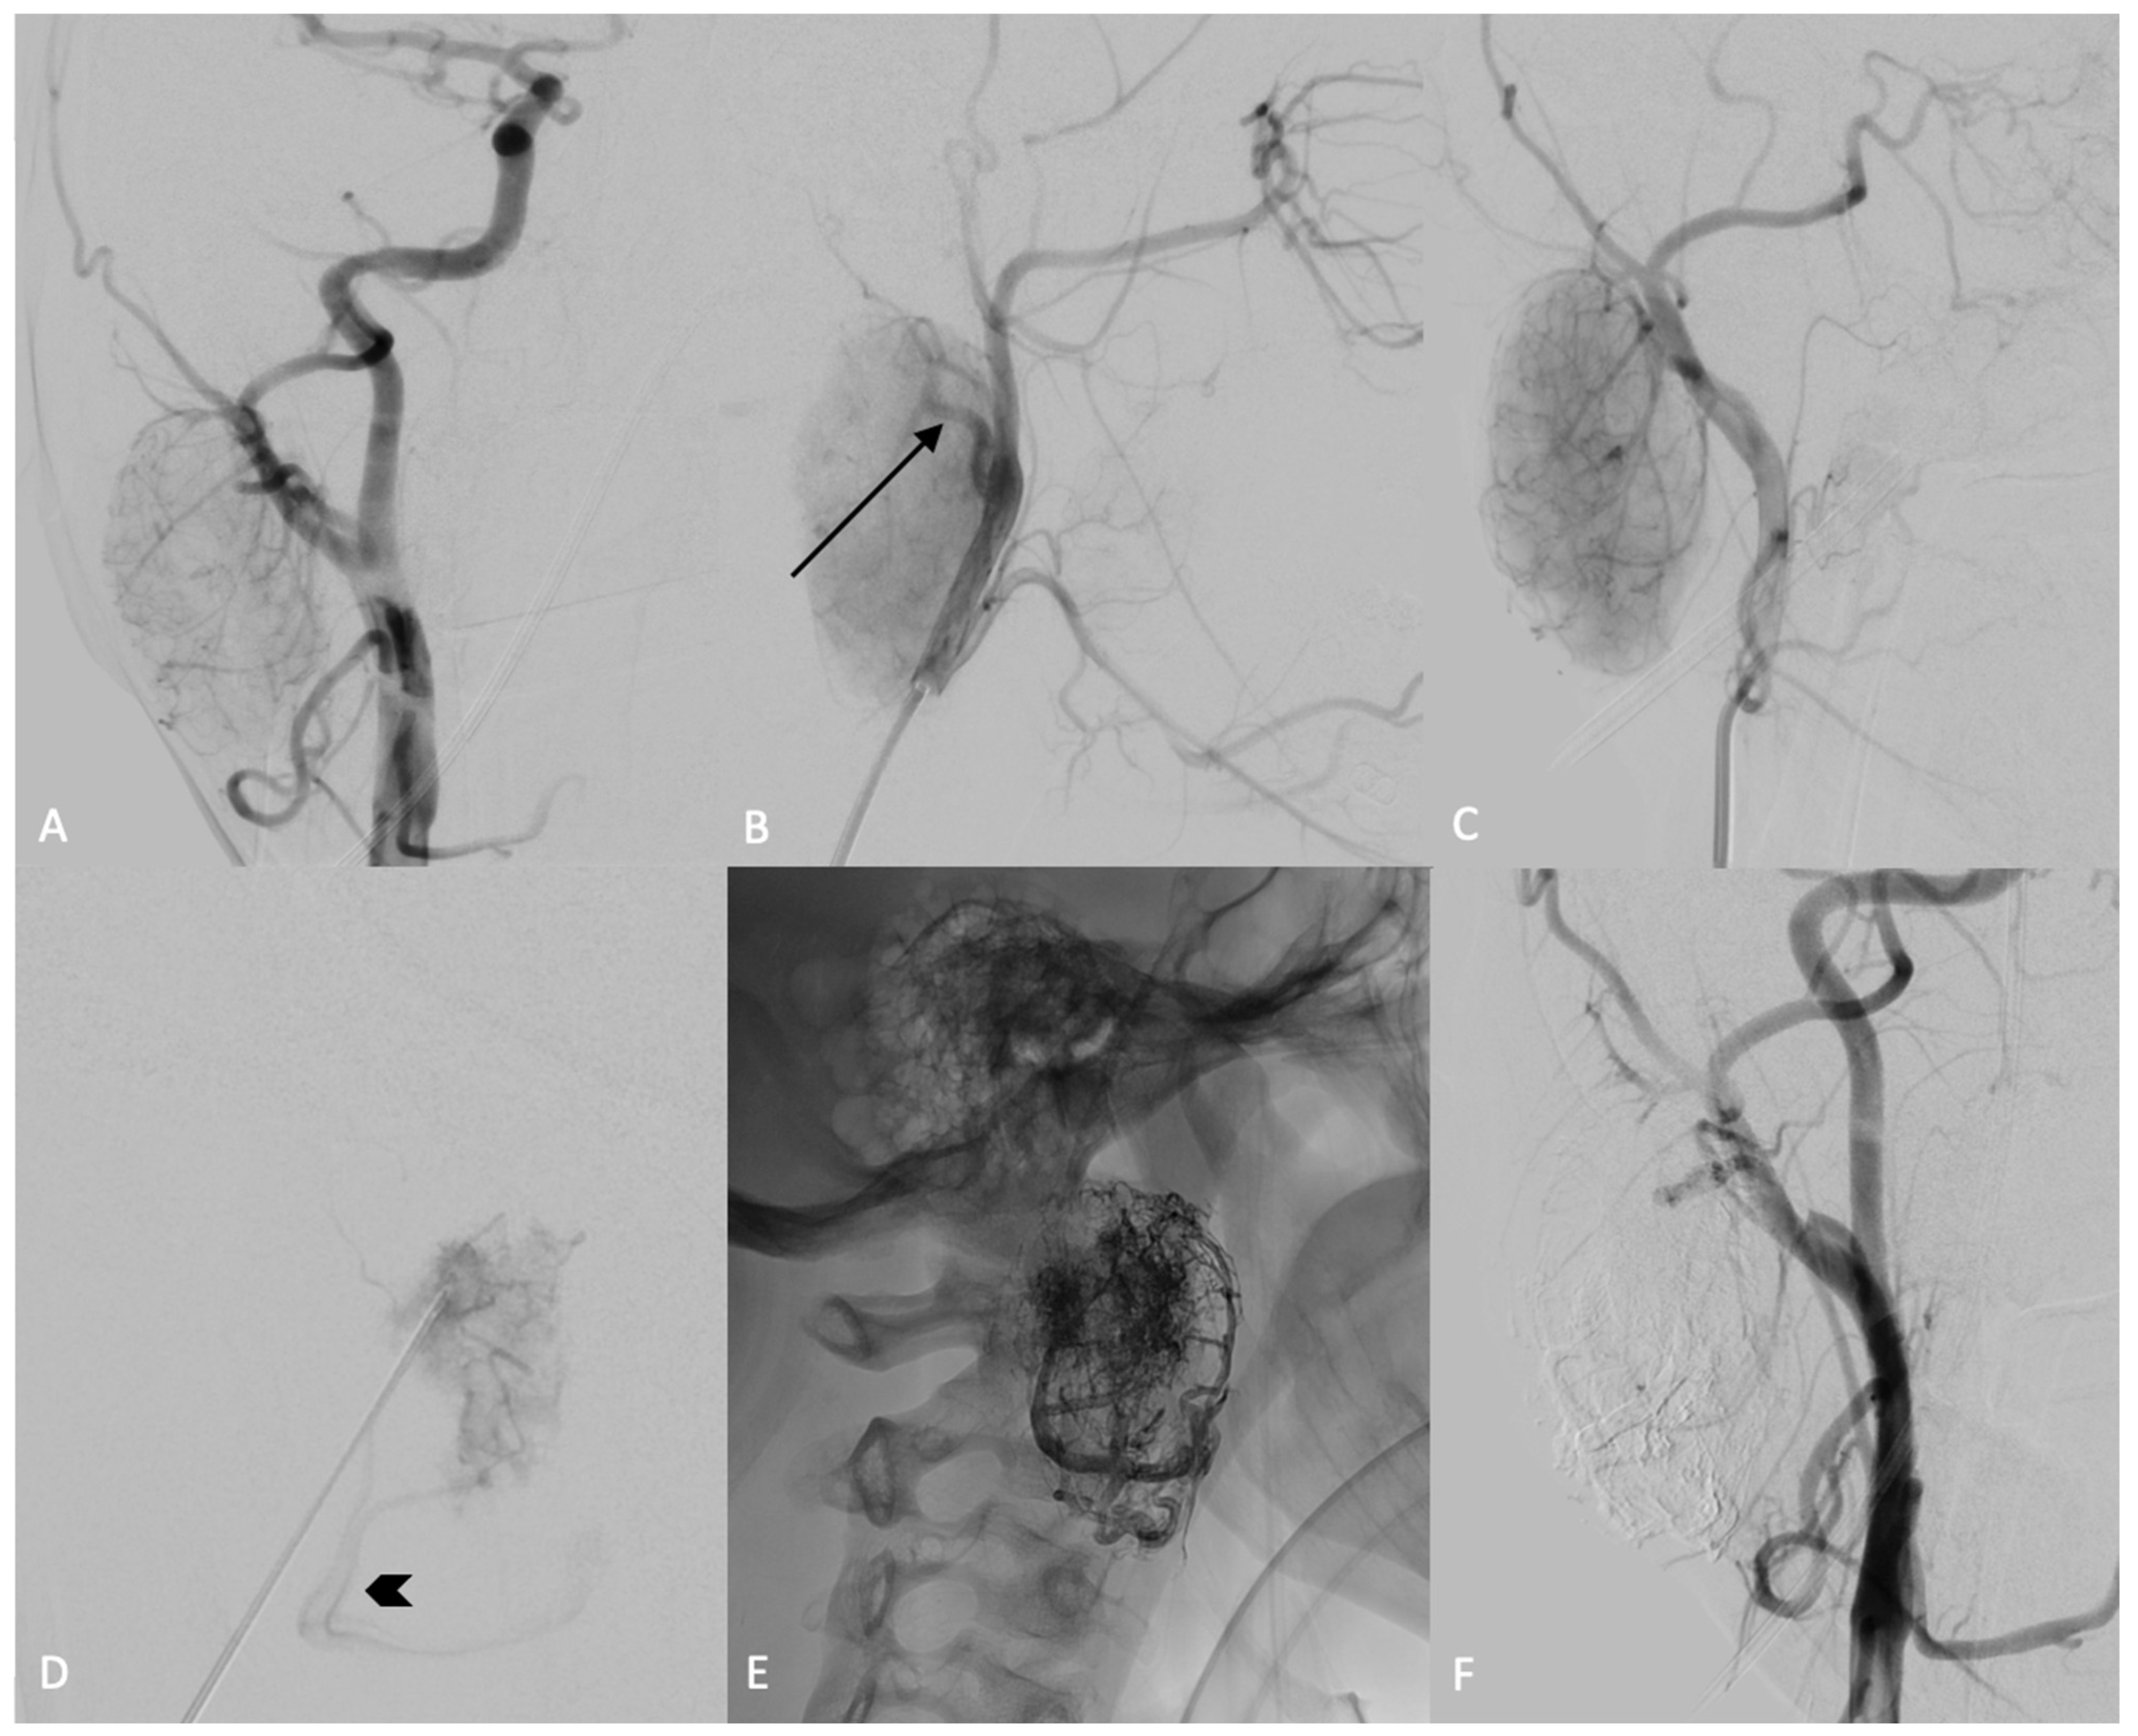

The preoperative embolization was conducted utilizing the direct puncture technique with SQUID 12, employing a biplane flat-panel angiographic system under general anesthesia (Figure 2). A preliminary diagnostic angiographic study was conducted to identify the feeding arteries supplying the mass and to assess for potential extracranial-to-intracranial anastomoses: the digital subtraction angiography (DSA) images revealed a single feeding artery originating from the posterior wall of the right external carotid artery, likely the posterior auricular artery. Additionally, a prominent venous drainage was observed via the facial vein. A 22-gauge needle was inserted into the core of the mass under the guidance of both ultrasound and fluoroscopy. An intra-tumoral angiogram was then conducted through the needle to verify its accurate positioning within the mass. Before injecting the embolic agent, a balloon microcatheter was inflated at the origin of the external carotid artery to prevent retrograde reflux in the internal carotid artery. Subsequently, SQUID 12 was injected through the needle into the mass under fluoroscopic control. At the end of the procedure, the final angiogram showed a total devascularization of the lesion, without any complications.

Figure 2.

DSA, anterior-posterior view of the right common carotid artery (A) and lateral (B) and oblique (C) views of the right external carotid artery. The injection showed the blush of the lesion laterally to the external carotid artery (A–C), with evidence of a hypertrophic posterior auricular artery (B, black arrow). The lesion was punctured and the needle position was confirmed by angiographic control through injection of the external carotid artery and by an intra-tumoral angiogram obtained after the injection of contrast medium through the needle (D); the main venous drainage of the lesion is clearly visible (D, black arrowhead). The lesion was slowly filled with SQUID 12, until obtaining complete occlusion (E), as confirmed by the absence of blush during the angiographic controls (F).